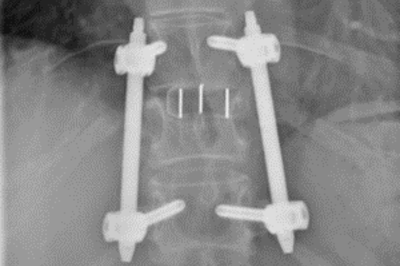

• Verschraubter Wirbelbruch

Röntgenbild verschraubter Wirbelbruch